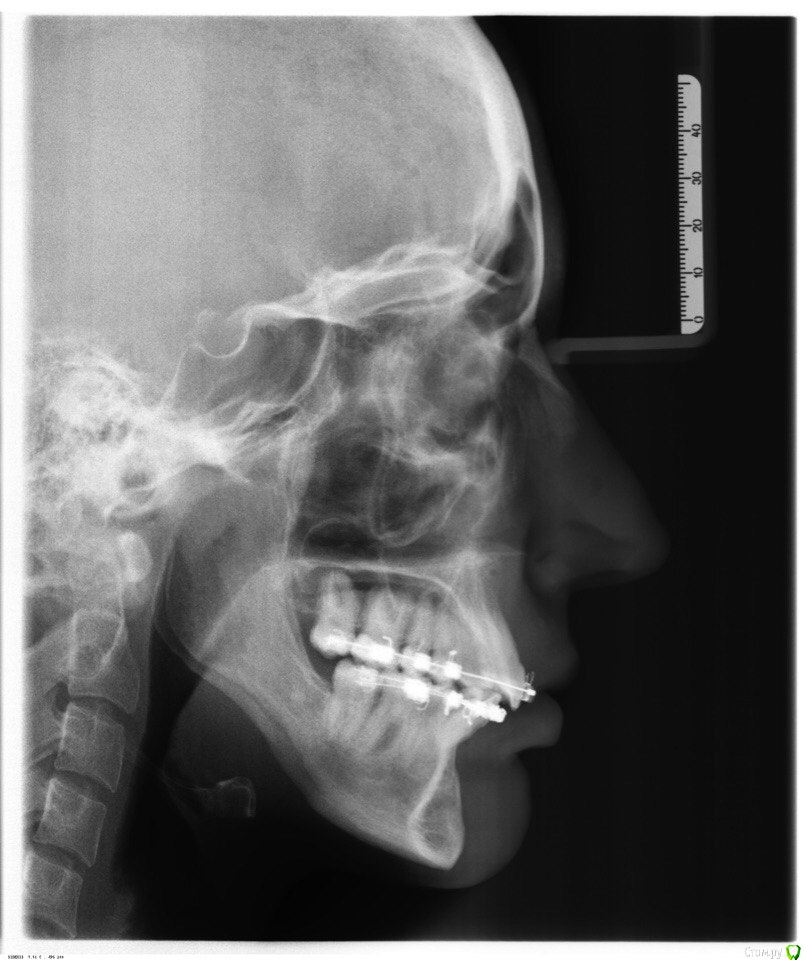

annurka Опубликовано 13 сентября, 2017 Автор Поделиться Опубликовано 13 сентября, 2017 (изменено) А До лечения есть ТРГ посмотреть? И фото какие-нибудь?есть трг сверху - сразу после остеотомии, снизу - через полгода после (когда резцы отошли друг от друга на 5мм) до лечения вообще точно делал ортодонт (снимки, слепки, фото), если в клинике это сохранили, я смогу сфотографировать. далее фото в процессе лечения - 4ки нижние еще не удалены, один хирург был готов так оперировать, другой сказал, что наклон нижних резцов неправильный и нужно как и было запланировано удалить 4ки, сепарации недостаточно.челюсть расслаблена как есть: НЧ подвинута к ВЧ для наглядности: есть фото слепков того периода, но форум ругается на слишком большой размер. если нужно - уменьшу залью) Изменено 13 сентября, 2017 пользователем annurka 1 Ссылка на комментарий

annurka Опубликовано 13 сентября, 2017 Автор Поделиться Опубликовано 13 сентября, 2017 (изменено) вот трг до начала лечения, фото к сожалению нет, если только из жизни) расшифровка трг ДО (где выделено синей ручкой) и недавнее Конечно контакты не идеальны, но если удалить 4ки наверху нижняя треть лица будет иметь довольно вогнутый вид спасибо за комментарий! а если сделать сепарацию резцов, тогда получится избежать вогнутости профиля? С ДВНЧС у вас сейчас проблемы остались? Можно рассмотреть совместно с врачом аппараты для выдвижения нижней челюсти,если тяги не справляются не было до недавнего времени - сейчас иногда болит в области сустава слева (видимо потому что контакты справа уже есть, а слева в процессе, поэтому нагрузка на челюсть неравномерная ?). до операции (но после начала лечения брекетами) сустав не беспокоил, надеюсь это просто период реабилитации.насчет аппаратов по выдвижению НЧ - спасибо, передам ортодонту.с6нимки к сожалению выполнены в разных клиниках, но мне казалось что если судить по трг через полгода, то НЧ там же, где была закреплена титановыми пластинами сразу после остеотомии (но проблема с резцами тогда уже возникла)... или мне так только кажется и произошел рецидив? думаете ее можно еще двинуть вперед? Изменено 13 сентября, 2017 пользователем annurka Ссылка на комментарий

Brigita Опубликовано 13 сентября, 2017 Поделиться Опубликовано 13 сентября, 2017 (изменено) Нет, я трг пока не могу рассчитать, чтобы это утверждать - на выходных только время будет, а пока с телефона смотрю. Предполагаю,да.Ну и плюс контакты зубы ищут правильные и смыкаются в разном положении Изменено 13 сентября, 2017 пользователем Brigita Ссылка на комментарий

annurka Опубликовано 14 сентября, 2017 Автор Поделиться Опубликовано 14 сентября, 2017 (изменено) Нет, я трг пока не могу рассчитать, чтобы это утверждать - на выходных только время будет, а пока с телефона смотрю. Предполагаю,да.Ну и плюс контакты зубы ищут правильные и смыкаются в разном положениивообще к обоим трг (до и нынешнее) я добавила расшифровку выше, или вы имеете ввиду те, что с титановыми конструкциями? мне все же хочется верить что это с зубами беда, и они новой челюсти не подходят, а не то что челюсть куда-то съехала.. в принципе, как и любому человеку, пережившему перемещение двух челюстей. еще есть такое фото, сделала его сразу после операции, швы не позволяли толком губы раскрыть, а рот нельзя было открывать на протяжении месяца, поэтому такое качество: http://i12.pixs.ru/thumbs/5/6/2/w1BZH71BWi_3410341_27523562.jpghttp://i12.pixs.ru/thumbs/5/5/3/4pJjOEAIq2_4300116_27523553.jpg там видно, что резцы сходятся как следует, а больше никаких контактов нет у других зубов. эластик (который скреплял от движения челюсть) в то же время создавал контакты клыков, носила только их месяца 4. фото через месяц после оп, тенденцию верхних резцов уже видно (но рот мне еще открывать нельзя было)http://i12.pixs.ru/thumbs/6/4/3/IMG5512JPG_8912889_27523643.jpghttp://i12.pixs.ru/thumbs/6/3/1/4pJjOEAIq2_7818185_27523631.jpghttp://i12.pixs.ru/thumbs/6/4/9/IMG5522JPG_8755357_27523649.jpghttp://i12.pixs.ru/thumbs/6/5/1/IMG5525JPG_1306296_27523651.jpg спустя 2 месяца после оп, стала жевать еду, открывать рот могла только на 2смhttp://i12.pixs.ru/thumbs/6/5/7/IMG9072JPG_6555113_27523657.jpghttp://i12.pixs.ru/thumbs/6/6/5/IMG9080JPG_2398494_27523665.jpghttp://i12.pixs.ru/thumbs/6/7/3/IMG9085JPG_1231417_27523673.jpg по ссылке доступно увеличенное изображение, спасибо Skip Изменено 14 сентября, 2017 пользователем annurka Ссылка на комментарий